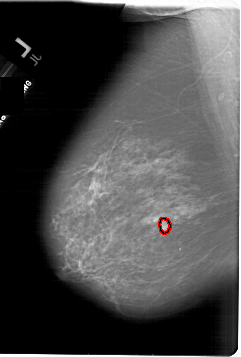

A_1821_1.LEFT_MLO

LEFT_MLO LINES 6781 PIXELS_PER_LINE 4576 BITS_PER_PIXEL 12 RESOLUTION 43.5 OVERLAY

FILE: A_1821_1.LEFT_MLO.OVERLAY

TOTAL_ABNORMALITIES 1

ABNORMALITY 1

LESION_TYPE MASS SHAPE IRREGULAR MARGINS SPICULATED

ASSESSMENT 5

SUBTLETY 5

PATHOLOGY MALIGNANT

TOTAL_OUTLINES 1

BOUNDARY